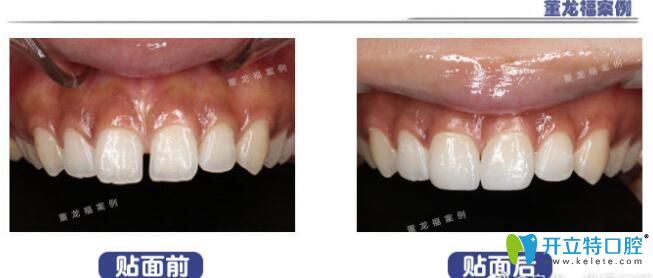

泉州維樂(lè)口腔門(mén)診部董龍福

董龍福

擅長(zhǎng):根管治療,活動(dòng)義齒,補(bǔ)牙

擅長(zhǎng):根管治療,活動(dòng)義齒,瓷貼面美白